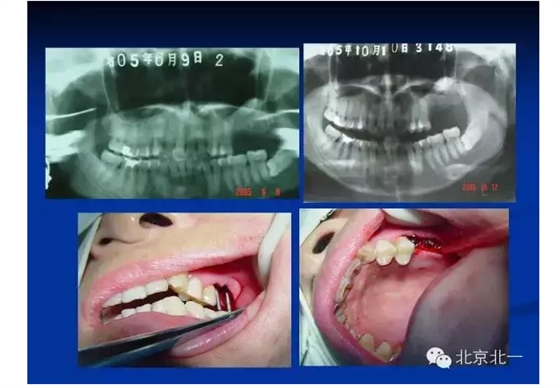

擅長(zhǎng):種植外科,尤其專長(zhǎng)復(fù)雜牙種植,自體骨移植同期種植,上頜竇底內(nèi)外提升同期種植技術(shù),美學(xué)區(qū)種植技術(shù),即刻種植外科與即刻負(fù)重技術(shù),軟組織成形外科種植技術(shù)及全口無牙頜ALL-ON-FOUR技術(shù),種植并發(fā)癥和種植急癥處置等手術(shù)治療,從事口腔頜面外科,正頜外科、頜面部整形、微創(chuàng)拔牙,笑氣無痛舒適種植十余年。

2014年榮獲全國(guó)第三屆BITC 口腔種植病例大獎(jiǎng)賽優(yōu)秀獎(jiǎng)。